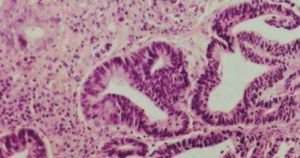

胃黏膜上皮異型增生主要發生在腸化的基礎上,也有一部分發生於胃小凹上皮等處。按照異型增生分化程度和範圍分為輕、中、重三級,即輕度是指炎症性及再生性良性異型增生病變;中度是指異型化較為明顯,接近胃癌的“臨界性病變”;重度是指異型化更為明顯,形態上難以和分化型癌相區別的異型增生。但良性的輕度異型改變與臨界性異型增生,以及惡性異型病變之間常是逐漸移行、轉化的過程,有時難以明確劃分。

近年來的研究對異型增生進行了進一步分類,按照組織來源可分為:①腺瘤型異型增生:來源於腸型上皮,起於黏膜淺層,癌變後為高分化腺癌;

②隱窩型異型增生:起源於隱窩,癌變後為中分化或高分化腺癌;

③再生型異型增生:見於黏膜缺損部的再生上皮,癌變後為低分化或未分化腺癌。異型增生是一動態過程,可以由輕度向重度發展,但也可以保持不變或逆轉,而重度異型增生則不易逆轉,可以發展成胃癌。因此,對重度異型增生應予及早處理。